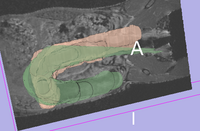

very rough surface models of colon help visualize misalignment very rough surface models of colon help visualize misalignment

original unregistered original, not registered